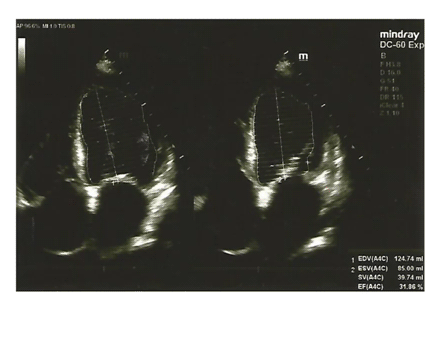

Bagaimana pompa jantung pasien?

Tanda panah menunjukkan adanya penurunan pompa jantung dengan nilai Ejection Fractional 31,86%. Sedangkan nilai normalnya adalah 53-77%.